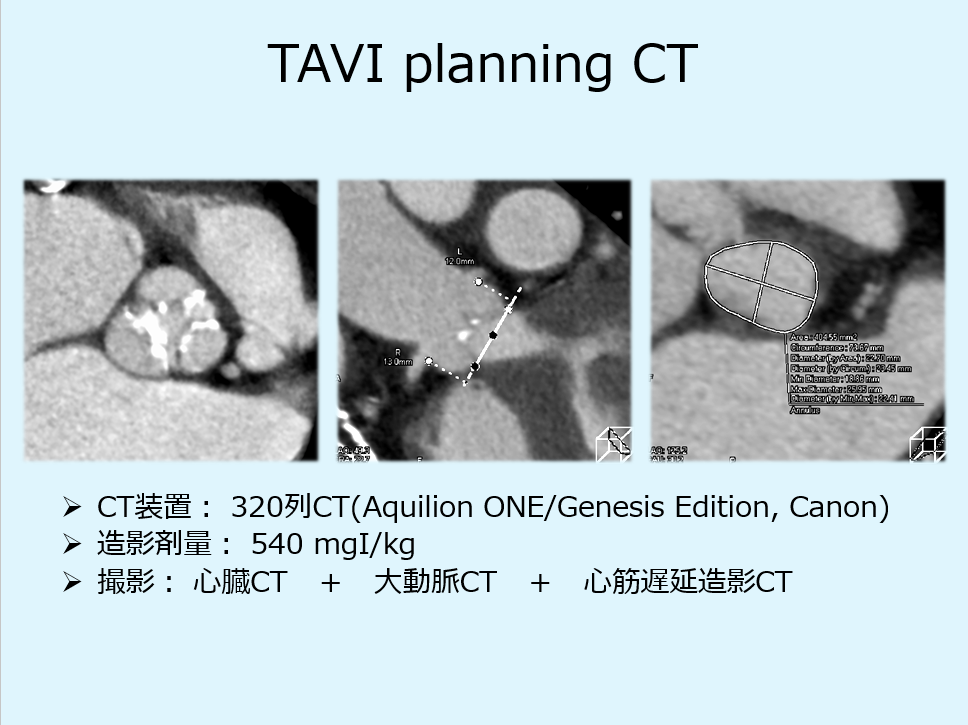

●TAVI適応の判断ではプランニングCTが必須ですが、当院では心筋遅延造影CTをルーチンで追加しています。(循環器科医の要望)

遅延造影撮影(造影剤注入から7分後)

遅延造影CTでの心筋評価は一定のエビデンスあり。TAVI症例は高齢であり被ばくの問題はない。造影剤の追加もない。